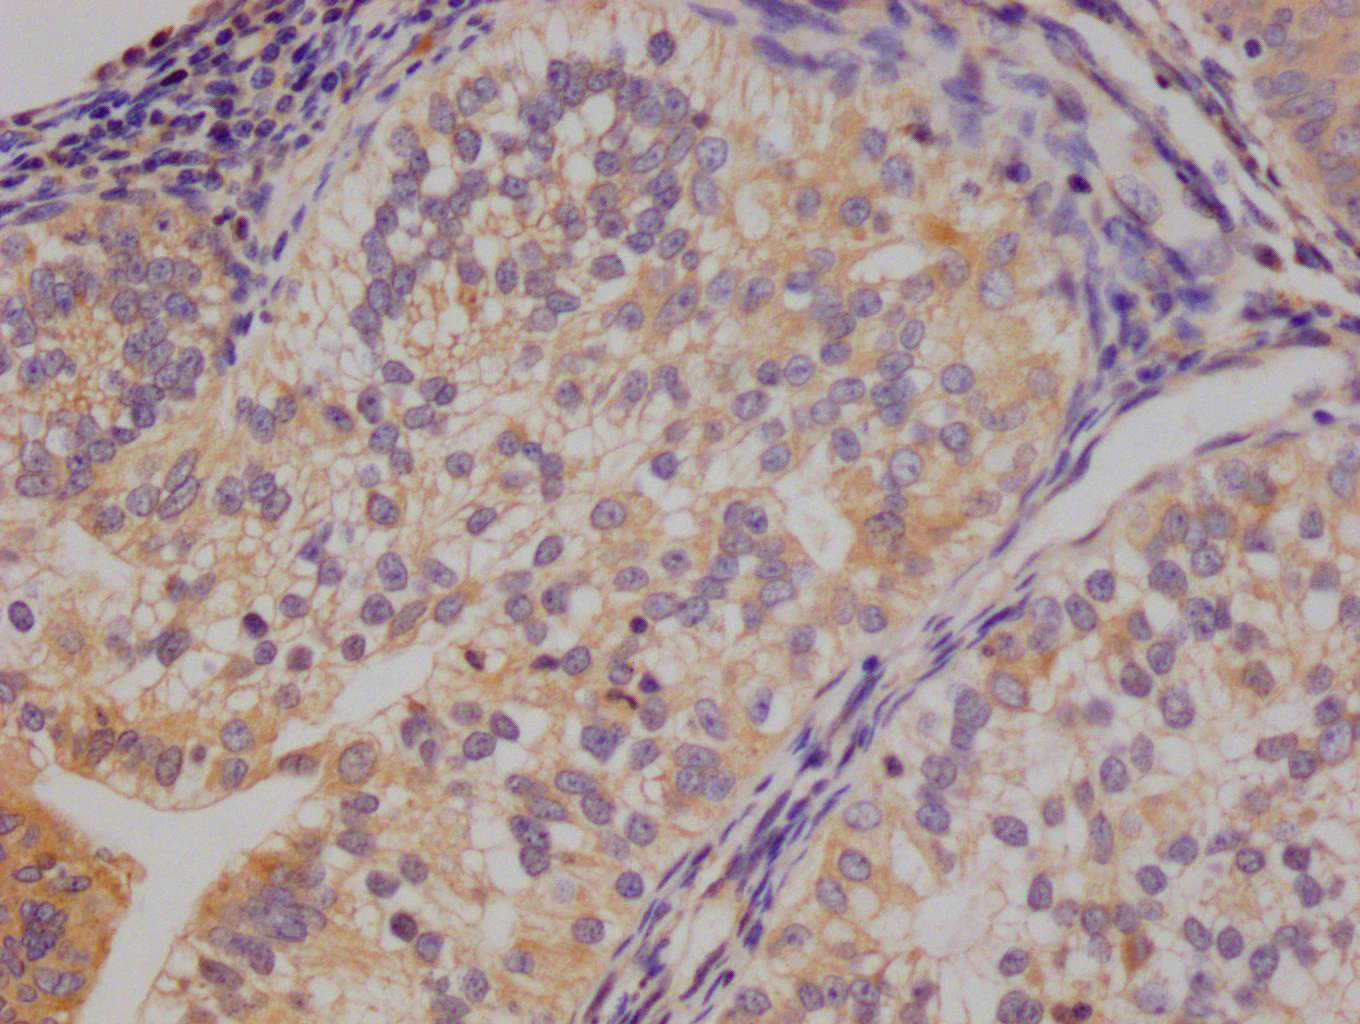

The image on the left is immunohistochemistry of paraffin-embedded Human thyroid cancer tissue using CSB-PA985822(ATP2A3 Antibody) at dilution 1/30, on the right is treated with synthetic peptide. (Original magnification: ×200)